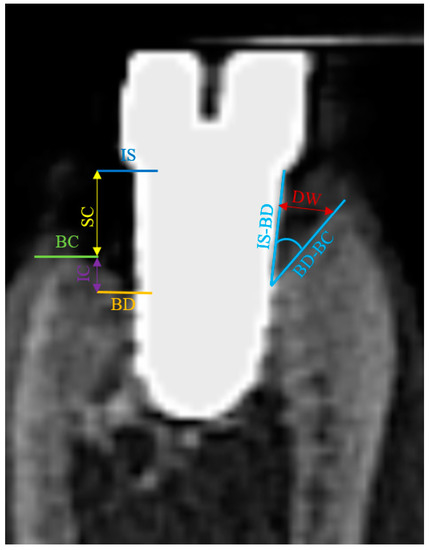

The following landmarks were identified in each sagittal image at all buccal, oral, mesial and distal aspects: IS (implant shoulder), the bottom of the bone defect (BD) and the alveolar bone crest (BC) (Figure 6). At both aspects, linear measurements were made by drawing a vertical line, following the long axis of the implant: from IS to BC (representing the supracrestal component of the defect-SC) and from BC to BD (representing the intrabony component of the defect-IC). In horizontal direction, where present, the defect width was measured as the linear distance from the implant surface to the alveolar bone crest, at buccal, oral, mesial and distal aspects.

The angulation of the peri-implant defects, as an additional measure of the extension of the bone destruction, was evaluated as well at the buccal, oral, mesial and distal aspects of the implants and represented the radiographic angle between the IS-BD and BD-BC segments.

Figure 6. Landmarks identified in each sagittal image at all buccal, oral, mesial and distal aspects: IS (implant shoulder), the bottom of the bone defect (BD), the alveolar bone crest (BC) and the angle between segments IS-BD and BD-BC. CBCT implant #5 (original magnification ×8).